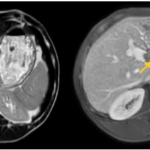

CASE LÂM SÀNG: CHẨN ĐOÁN BỆNH NHÂN MẮC HAI UNG THƯ: GIST RUỘT NON VÀ UNG THƯ TUYẾN GIÁP TẠI TRUNG TÂM Y HỌC HẠT NHÂN VÀ UNG BƯỚU, BỆNH VIỆN BẠCH MAI

Ca lâm sàng